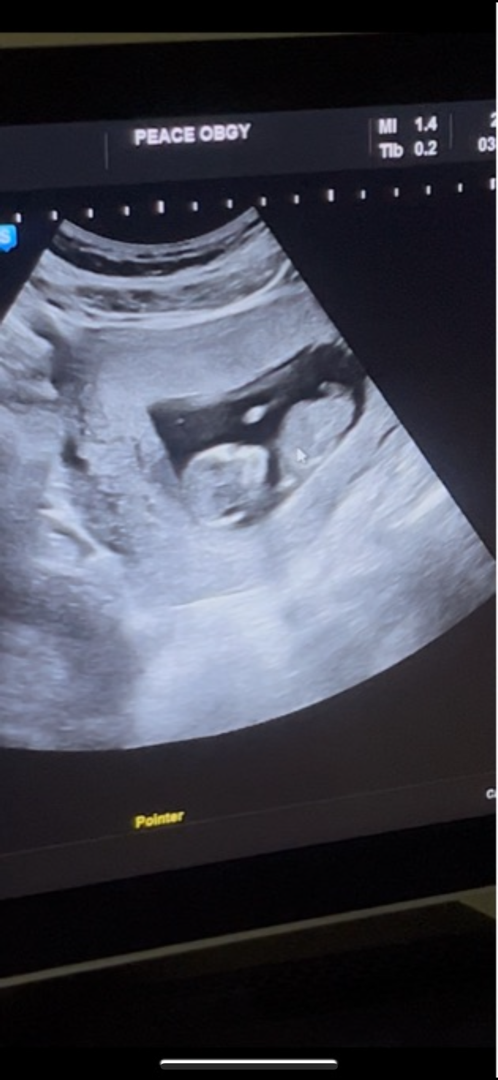

12주차 각도법 한번 봐주세요🩷

각도법 참견 부탁드립니당

이 사진으로는 보기 어려워요! ㅠ